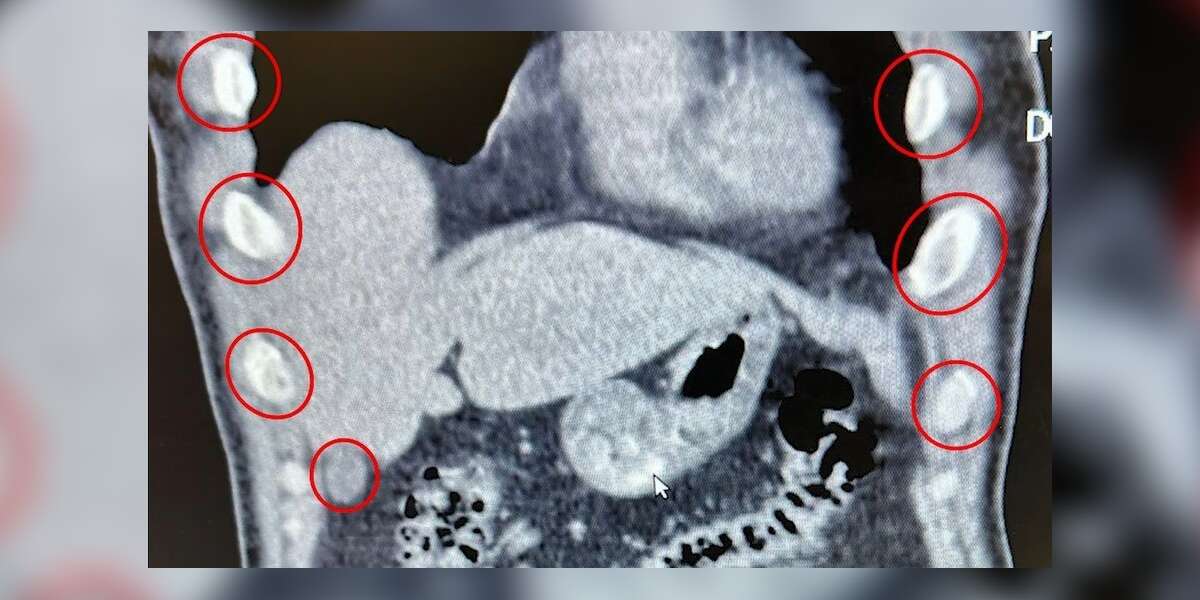

Şok Operasyon: Midelerinden 136 Kapsül Uyuşturucu Çıktı